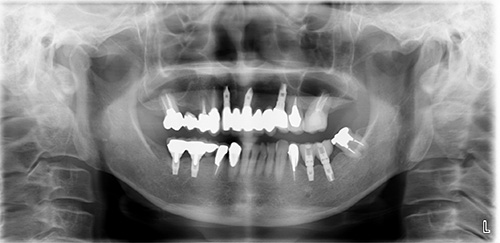

レントゲン像です。

After

術後のCT画像が重要です。シュミレーションとほとんど同じ位置に埋入できました。